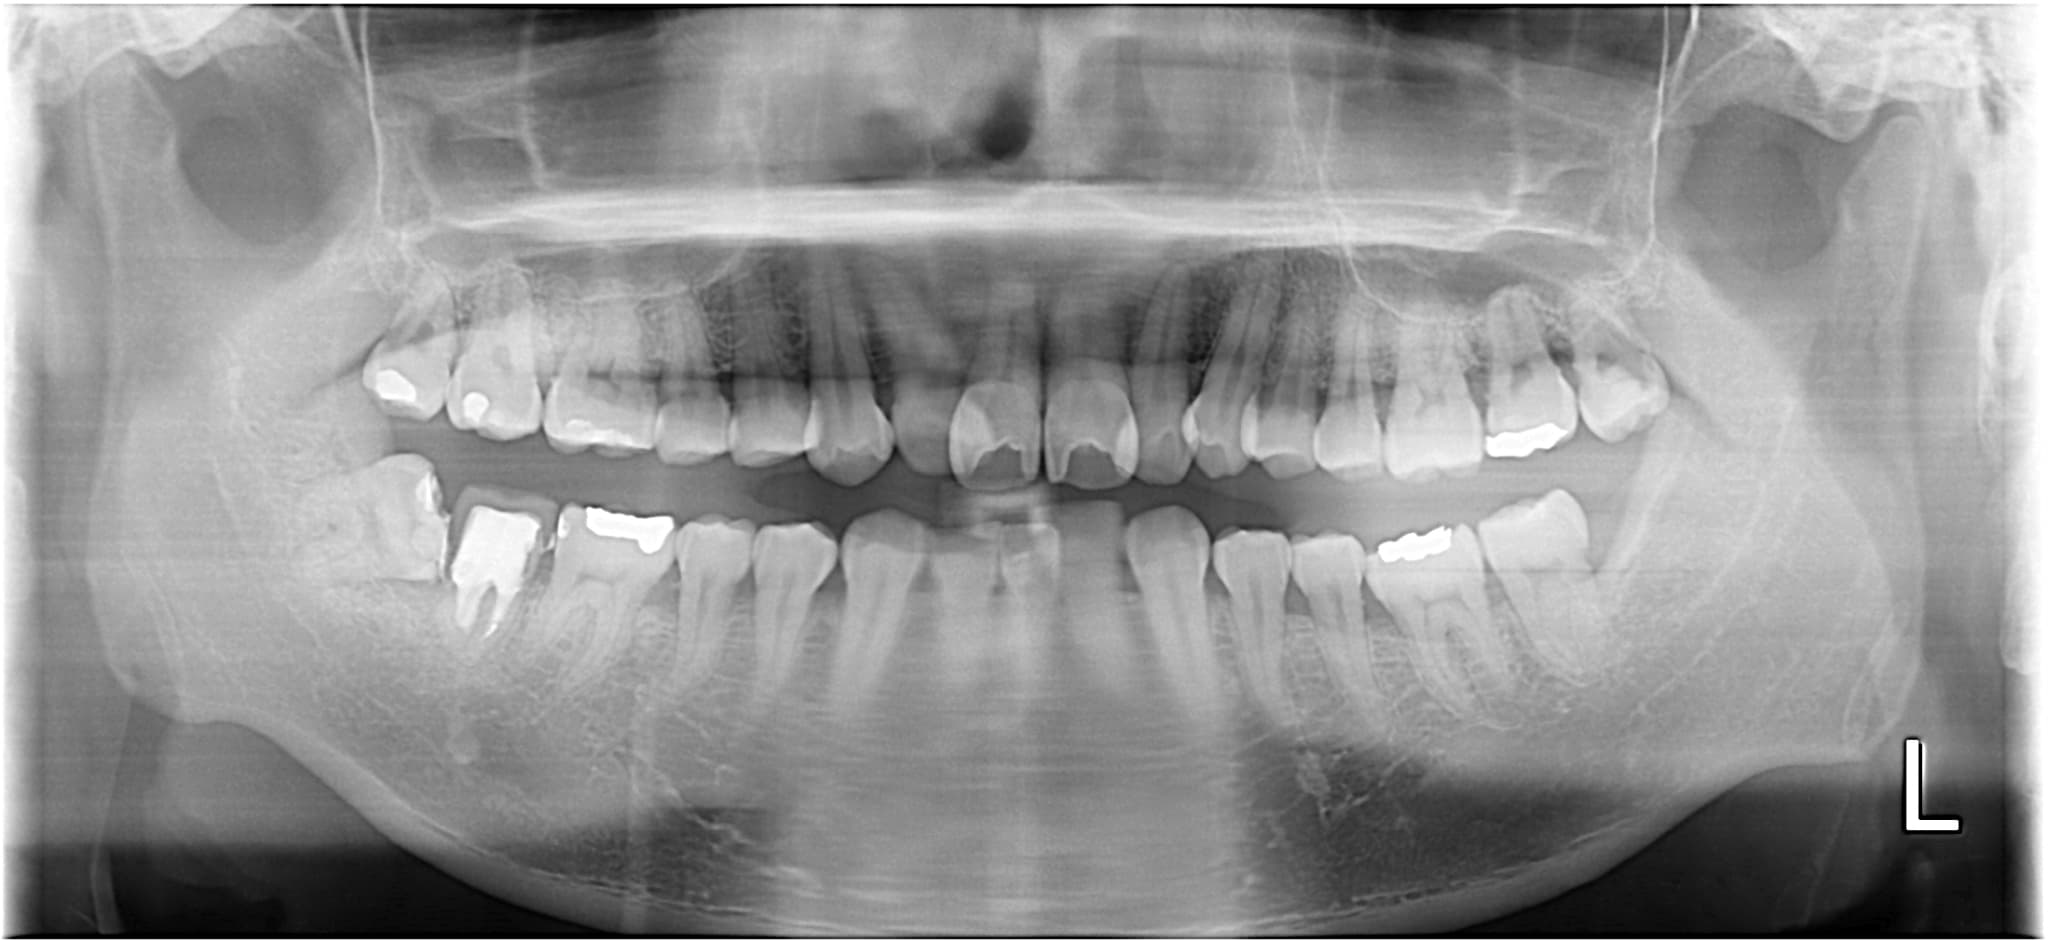

| 術名 | 親知らずの抜歯 |

|---|---|

| 生え方 | 右下:斜め、真横に生えている 左:まっすぐキレイ |

| 年齢 | 30代 |

| 性別 | 男性 |

| 主訴 | 腫れ |

| 診断名 | Pericoぺリコ(智歯周囲炎) |

| 治療内容 | 親知らずの抜歯 |

| 治療期間 | 施術:1日(経過観察:1か月後) |

| 治療費用 | 6,000円 ※保険適用3割負担の場合(CT/パノラマレントゲン含む) |

| リスク・副作用 | ・術後の腫れ ・ドライソケット |